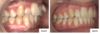

Monsieur G., 36 ans

Palais étroit, béance antérieure, encombrement bimaxillaire, "couloirs noirs" sur les cotés du sourire

- Gouttières d'alignement Invisalign (durée : 30 mois) pour fermeture de la béance et restauration d'une occlusion équilibrée (contacts postérieurs et antérieurs, guide antérieur fonctionnel). Embellissement du sourire grâce à l'alignement des dents et l'élargissement des arcades.

Traitement avec gouttières Invisalign avant - pendant et après